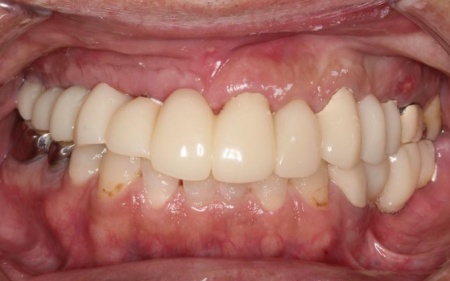

治療後